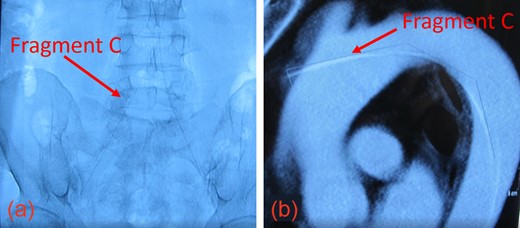

Upon presentation, we found moderate (55%) stenosis in the right common carotid artery (CCA) and severe (90%) stenosis in the ICA inferior to Stent 1. The most superior of the three guidewire fragments (Fragment A), still attached to the EPD, was compressed by Stent 2 and extended into the CCA (Fig. 1c and d). The middle piece (Fragment B) was adhered to the right CCA wall by local fibrin deposits. The inferior fragment (Fragment C) extended from the right femoral artery to the thoracic aorta, where it punctured the proximal aortic arch wall (Fig. 2a and b). Thrombus had also formed along the entire 1-meter length of Fragment C.

(a) The inferior aspect of Fragment C extended down to the femoral artery. (b) The superior aspect of Fragment C penetrated the thoracic aorta.